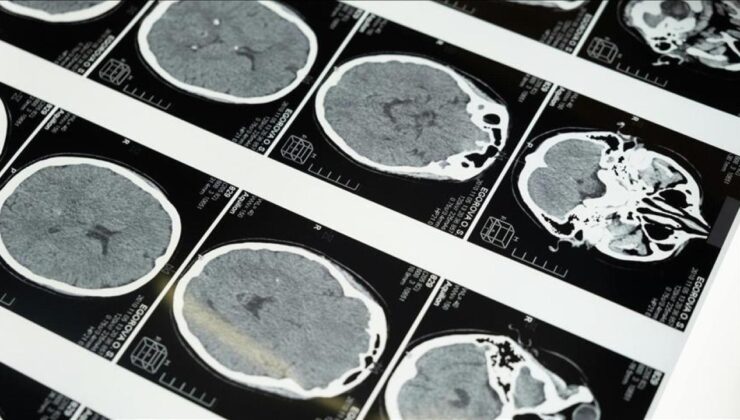

İstanbul’da düzenlenen 1. Dünya Girişimsel Nöroloji ve Nöroşirürji Kongresi’nin (WINNC 2025) düzenleme komitesinde yer alan Eskişehir Osmangazi Üniversitesi Tıp Fakültesi Nöroloji Ana Bilim Dalı Öğretim Üyesi ve İnme Merkezi Sorumlusu Prof. Dr. Atilla Özcan Özdemir, inmenin beyin damarlarının tıkanması (iskemik) ve beyin kanaması şeklinde gelişen iki türünün olduğunu söyledi.İskemik inmenin dünyada ve Türkiye’de sık görüldüğünü, özellikle kadınlarda görülme sıklığının arttığını ve meme kanserinden daha yaygın hale geldiğini belirten Özdemir, inmenin başlıca ölüm nedenlerinden biri olduğunu ve erişkin yaşta kazanılmış engelliliğin en sık nedeni olması nedeniyle ciddi bir halk sağlığı sorunu haline geldiğini kaydetti.Prof. Dr. Özdemir, “ileri yaş hastalığı” olarak bilinse de inme görülenlerin ortalamasının 60’lı yaşlara kaydığını, genç yaşta geçirilen inmelerde de artış yaşandığını aktardı.Aynı zamanda kalp hastalıklarının da önemli inme risk faktörlerinden olduğuna dikkati çeken Özdemir, kalp kaynaklı pıhtıların beyin damarını tıkaması sonucu inmeye neden olabileceğini vurguladı.Yaşam faktörlerinin kontrol altına alınmamasının da inmeye neden olabileceğinin altını çizen Özdemir, “Şeker hastalığı, egzersiz yapılmaması, stres, viral enfeksiyon sıklığının artması inmenin daha genç yaşlarda görülme nedenlerinden sayılabilir. Sigara kullanımı da çok önemli faktörlerden birisi. İnme tıpkı kalp krizi gibi birçok risk faktörü sonucu ortaya çıkan bir hastalıktır. Bu risk faktörleriyle ortaya çıkan kalp hastalıkları da inmeye neden olabilir. Tabii buradaki sıkıntı inme farkındalığı. Bu farkındalık, dünyada ve ülkemizde iyi değil.” ifadelerini kullandı.Prof. Dr. Özdemir, ani gelişen konuşma bozukluğu, yüzde kayma veya kolda güçsüzlük yakınmalarından bir veya daha fazlasının varlığında inmenin akla getirilmesi, zaman kaybetmeden 112’nin aranması gerektiğini kaydetti.Türkiye’de inme tedavisinde önemli gelişmeler yaşandığına değinen Özdemir, şöyle devam etti:”Özellikle pıhtıyla tıkanan beyin damarının açılmasıyla ilgili stratejiler gelişti. İnmede erken dönemde yapılan damar açma tedavileri konusunda ülke olarak iyi durumdayız. İnme tedavisinde pıhtıyla tıkalı beyin damarının anjiyo yoluyla açılması mümkün. Böylelikle hastanın 3 ay sonra, 1 yıl sonra kendi işini yapabilecek hale getirilmesi sağlanabiliyor. İnme merkezlerinde uygulanabilen bu işlemi ilk 24 saat içerisinde belirli hasta gruplarına yapabiliyoruz. İlk 24 saat çok kritik, bu müdahaleler de sadece inme merkezlerinde yapılabiliyor.”Prof. Dr. Özdemir, inmede erken müdahaleyle felç kalmanın önüne geçildiğini, 112 Acil Sağlık ekiplerinin hastayı inme merkezine hemen ulaştırması gerektiğini dile getirdi.Ambulans personelinin bu konularda eğitildiğini belirten Özdemir, “112’nin hastayı tanıması ve inme merkezine ulaştırması önemlidir. Ulaşamazsa hastaya müdahale mümkün olmuyor. Hastanın yüzüne soğuk su çarpmak ve beklemek, soğan veya kolonya koklatmak, ‘Bir yatayım bakayım geçer mi?’ demek yapılmaması gereken hatalar. Bunları demeden saydığım bulgular varsa mutlaka inme olarak kabul etmemiz ve 112’yi aramamız lazım. 112 aracılığıyla hastalar, uygun tedavinin uygulanabildiği inme merkezlerine ulaştırılmaktadır.” diye konuştu.GENÇLERDE MASAJLA GELEN İNME UYARISIGençlerde de son yıllarda inmenin arttığına dikkati çeken Prof. Dr. Özdemir, bu yaş grubunda kalp hastalığı ile damar yırtılmasının en büyük tehlikelerden bir olduğunu vurguladı.Özdemir, şah damarı ve boyun arkasındaki beyni besleyen damarların yırtılmasının kişilerin yapılarından kaynaklı olduğunun altını çizerek, sözlerini şöyle tamamladı:”İkinci önemli neden de boyuna yapılan masajlar. Boynumuza dokundurtmamamız lazım. Oradan damarlar geçiyor ve masajlar sırasında damar yırtılıyor. Yırtılan damar içerisinde oluşan pıhtı beyin damarlarını tıkayıp inmeye neden olabiliyor. Kafa hareketleri, boyun kütletmeler ehil olmayan kişilerce yapılan masajlar, bunların hepsi yırtılmaya neden oluyor. Bu yüzden lütfen boynumuza masaj yaptırmayalım. Özellikle gençlerde bu şekilde inme vakası sıklıkla görülüyor. Yalnızca bizim kliniğimize bile ayda 1-2 olmak üzere bu şekilde vaka geliyor. Gribal enfeksiyonlarda kullanılan burun damlaları da hipertansiyon hastalarında ani tansiyon yükselmesine, beyin kanamasına ve inmeye neden olabiliyor. Hipertansiyon hastaları bu damlalardan uzak durmalı.”